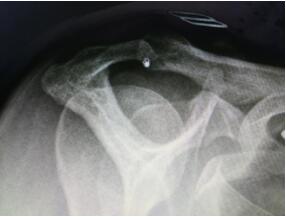

“患了肩峰撞擊綜合征,通常只要適量運(yùn)動(dòng),經(jīng)過(guò)充分休息是不會(huì)發(fā)生肩痛的。但是有一類人群應(yīng)當(dāng)注意,那就是三型肩峰?!崩畋蛑魅芜M(jìn)一步說(shuō)到,肩峰撞擊綜合征分為三種類型,一型為平坦型,在肩關(guān)節(jié)外展活動(dòng)時(shí)發(fā)生撞擊或撞擊的程度較輕;二型為肩峰弧形,在肩關(guān)節(jié)外展活動(dòng)時(shí)發(fā)生撞擊或撞擊的程度較一型要重,多為40歲以上中老年患者;三型肩峰為鉤型肩峰,在肩關(guān)節(jié)外展活動(dòng)時(shí)發(fā)生撞擊或撞擊的程度較高。89%的三型肩峰存在肩峰撞擊,撞擊后容易造成肩峰下肩袖肌腱撕裂。

???????????????????X片檢查發(fā)現(xiàn)患者為三型肩峰